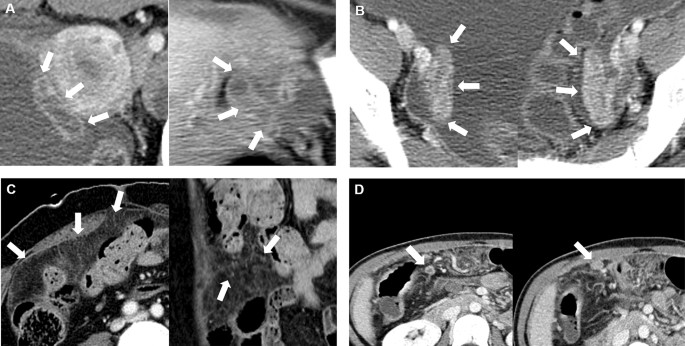

We defined the peritoneal macronodules when there were any peritoneal nodules or masses the size ofāā„ā5Ā mm. In contrast, the remaining cases showed diffuse peritoneal infiltration and nodularity without discrete peritoneal nodules or massesāā„ā5Ā mm as peritoneal micronodules. Representative cases for each imaging feature are shown in Fig.Ā 2.

Representative cases of CT imaging features. (A) Hydrosalpinx, (B) fallopian tube enhancement, (C) peritoneal micronodule, and (D) peritoneal macronodule.